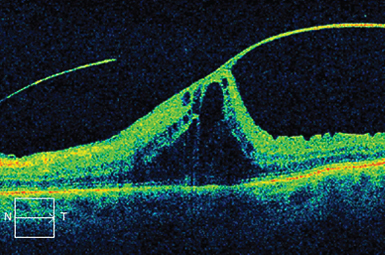

Vitreo-macular Traction

Incomplete vitreous separation sometimes tugs on the macula. If non-resolving, surgery (or intravitreal medicine) usually rectifies this condition.

Image courtesy of Heidelberg Engineering, Inc.